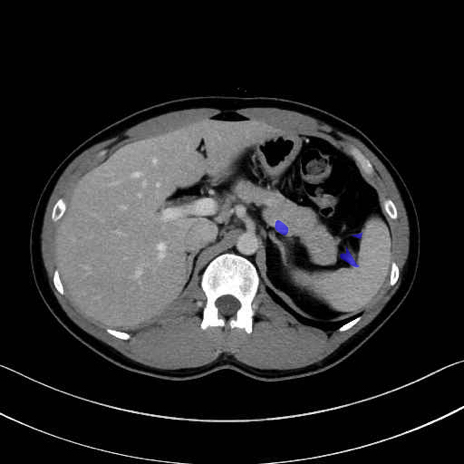

脾静脈の画像解剖

■起始:脾門で脾静脈枝が合流して本幹を形成。

■走行:膵体尾部の後面溝を右走し、膵頸部の後方で上腸間膜静脈(SMV)と合流して門脈を形成。

■主な流入枝:短胃静脈・左胃大網静脈・膵静脈、そして下腸間膜静脈(IMV)(変異あり)。